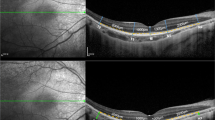

Measurement of mean global RNFL thickness in patients with RPGR-associated RP revealed significantly higher values compared to controls (128 µm vs. 96 µm; p < 0.0001). On a topographic level, the RNFL was significantly thickened in all sectors except for the nasal inferior sector (109.3 µm vs.107.8 µm) (Fig. 2a). The greatest thickness difference was seen in the temporal sector (136.9 µm vs.71.7 µm). In contrast, thinning of the outer retinal layers was observed in patients with RPGR-associated RP compared to controls. This resulted in significantly lower values of the whole retinal thickness in RPGR-associated RP globally (231 µm vs.309 µm; p < 0.0001) and in all different sectors (all, p < 0.0001) (Fig. 2b).

Representative peripapillary OCT scans of a healthy control and of a patient with RPGR-associated retinitis pigmentosa (top); sector-wise comparison of the retinal nerve fiber layer thickness (a) and whole retinal thickness (b) between RPGR-associated retinitis pigmentosa and controls. *p < 0.05, **p < 0.005, ***p < 0.0005, ****p < 0.0001